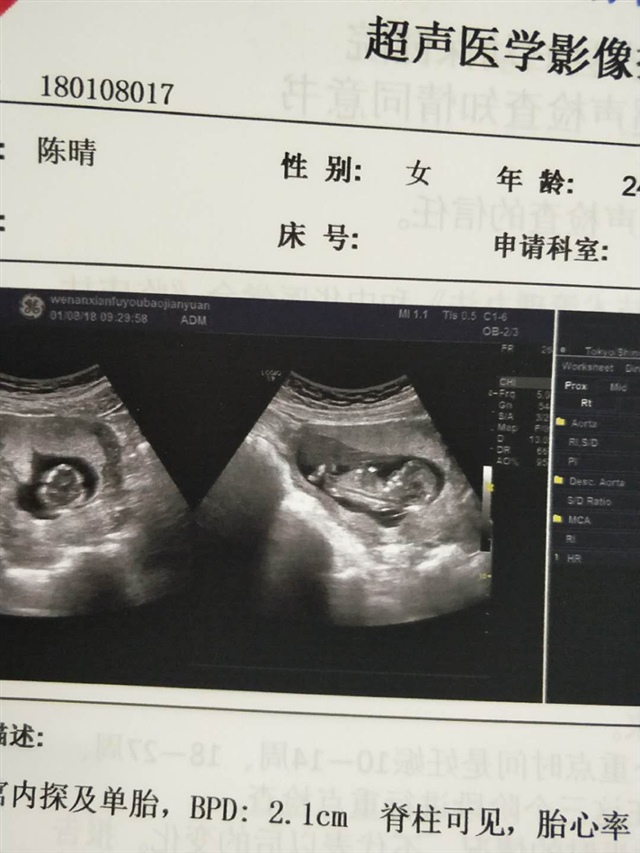

孕11周+5天

男孩